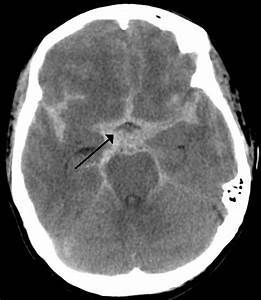

Paciente com quadro de cefaleia súbita, classificada como pior da vida, sonolência, diminuição do nivel de consciência, rigidez de nuca que surge 12 horas após inicio da cefaleia e sem sinal fical…

Diagnóstico, exame complementar, tratamento

HEMORRAGIA SUBARACOIDE

Ruptura de uma das artérias do polígono de Willis (+ comum comunicante anterior)

TC de crânio sem contraste: Hiperdensidade no espaço subaracnóide, sangue se mistura com liquor.

Se TC normal: PL (xantocromia)

Realizar angioTC ou arteriografia para localizar aneurisma